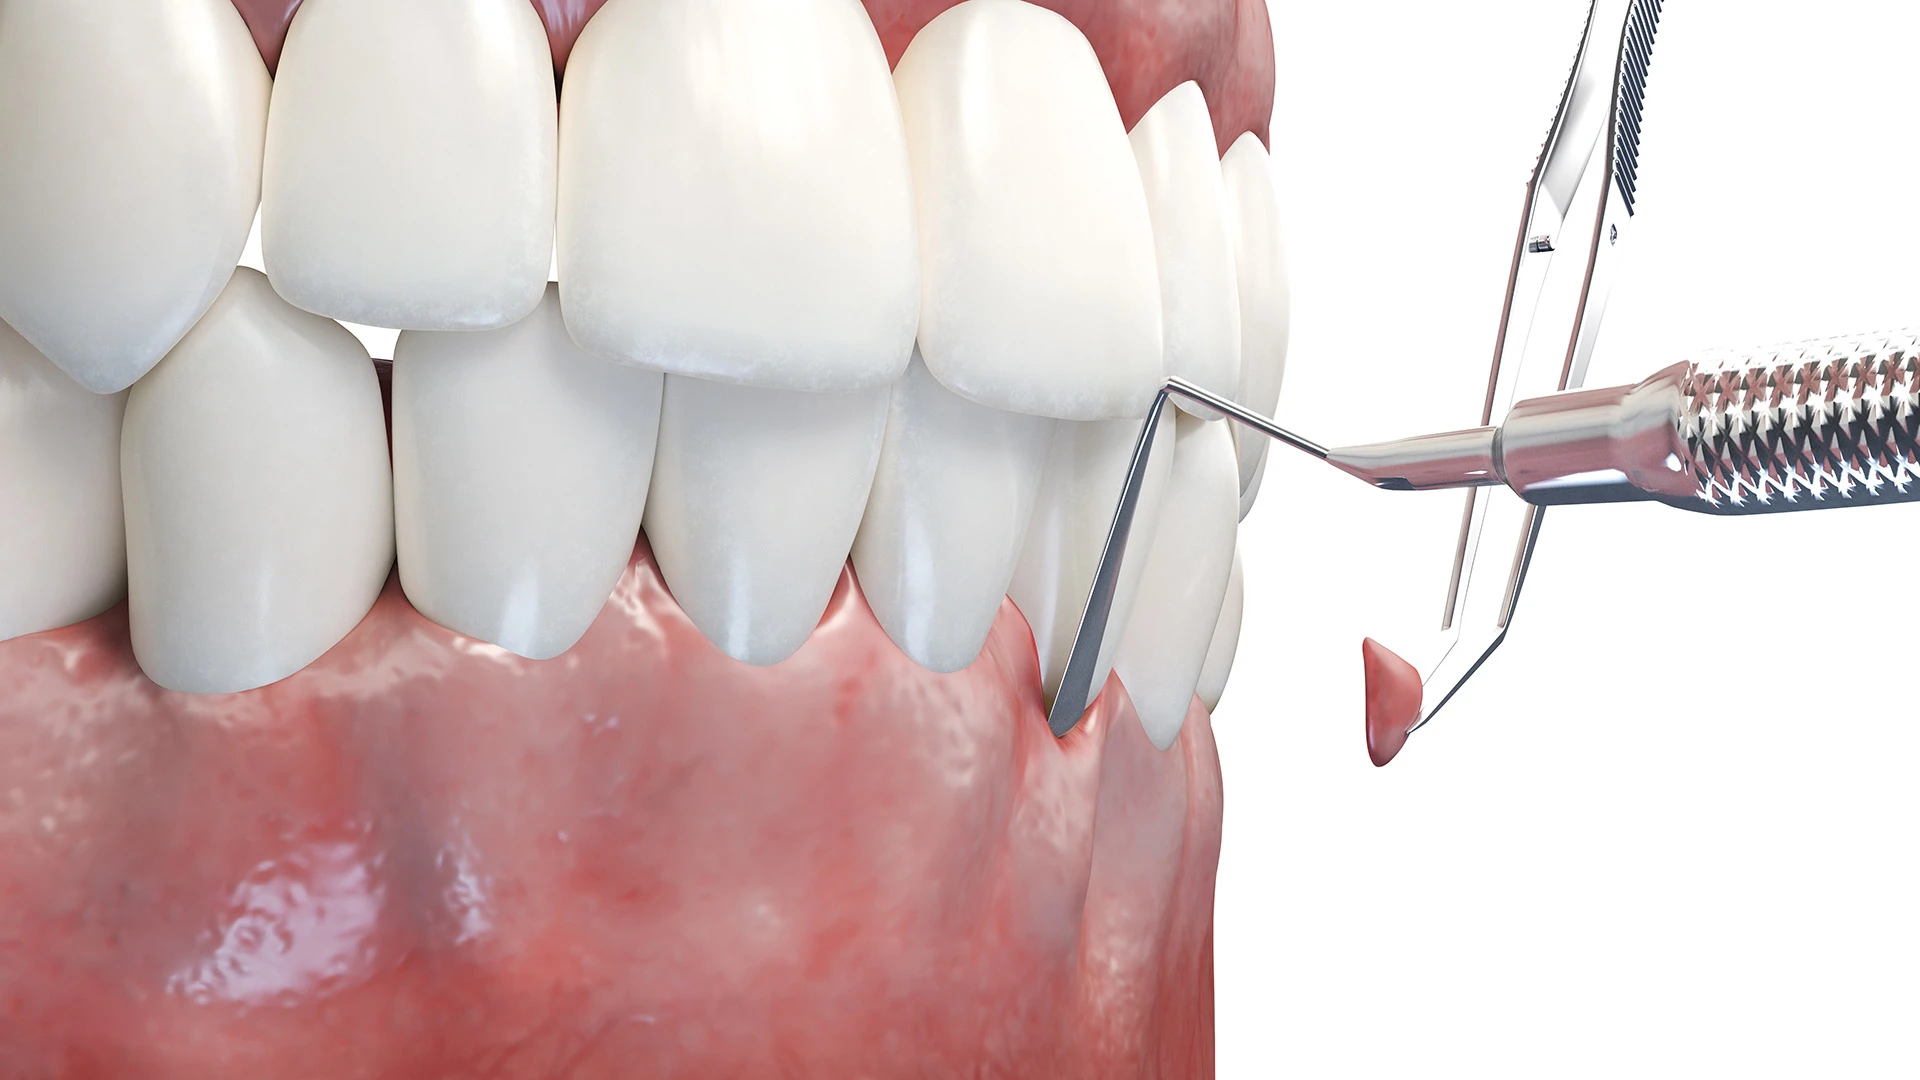

Soft Tissue Grafting

As a common symptom of periodontal disease, receding gums may cause insecurity, sensitivity, and even discomfort. We want you to feel comfortable in your smile, and soft tissue grafting is a great solution to re-establish your gum line. Not only will you be more confident, but it prevents further deterioration. Get back to a healthy, comfortable smile by booking your first consultation.